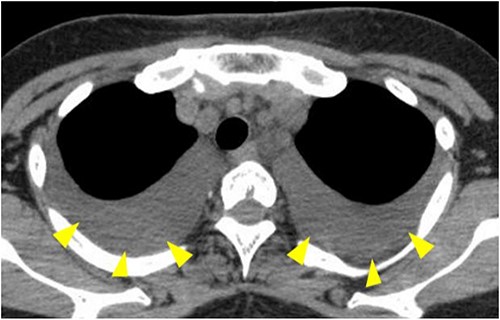

The postoperative course was uneventful; however, rapid enlargement of left cervical lymph nodes was observed at 1 month after surgery. Contrast-enhanced CT showed enlarged left cervical lymph nodes with ring enhancement, and a diagnosis of secondary cervical lymph node metastasis was made (Fig. 1). Left radical neck dissection was performed under general anesthesia in October 2014, and a thick thoracic duct was found in the supraclavicular fossa during surgery. There was no leakage of lymph after ligation and cutting of the thoracic duct (Fig. 2), and the operation was completed following placement of three suction drains in the left neck.

Contrast-enhanced CT is showing enlarged left cervical lymph nodes with ring enhancement (arrowheads).

CT showing pleural effusion in both lower lung fields (arrowheads).